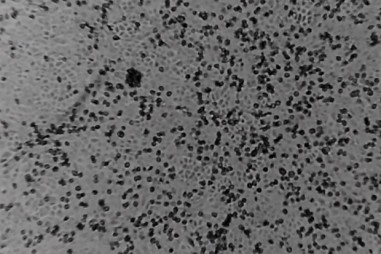

TNNN - Một dẫn xuất của cây artemisinin annua (cây thanh hao hoa vàng), còn được gọi là cây ngải ngọt hoặc cây ngải cứu, từ lâu đã được sử dụng trong...

TNNN - Các nhà nghiên cứu Thụy Sĩ và Anh đã thành công trong việc phát triển một loại thuốc kháng virus sử dụng các dẫn xuất glucose tự nhiên, được...